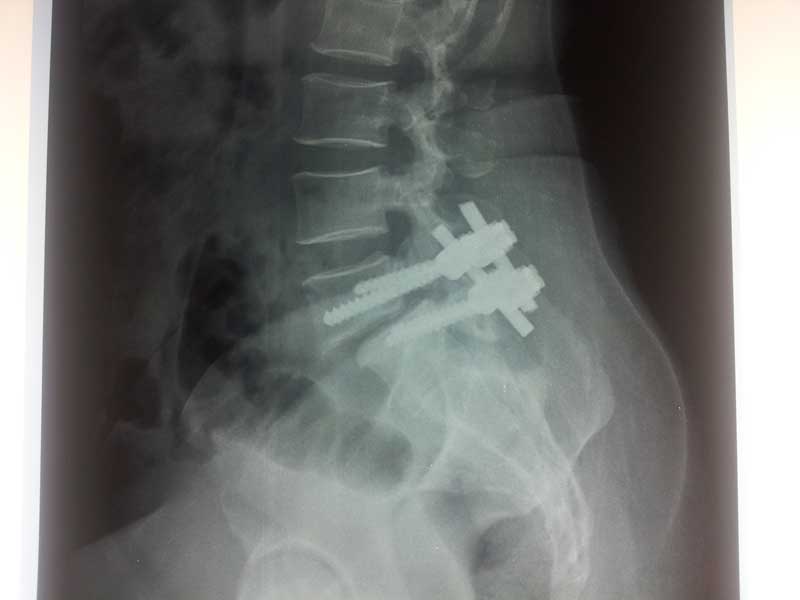

POST OP XRAY LAT

Spine Fixation Lumbar Spine

• Spine Fixation Lumbar Spine

post op x ray lat 1